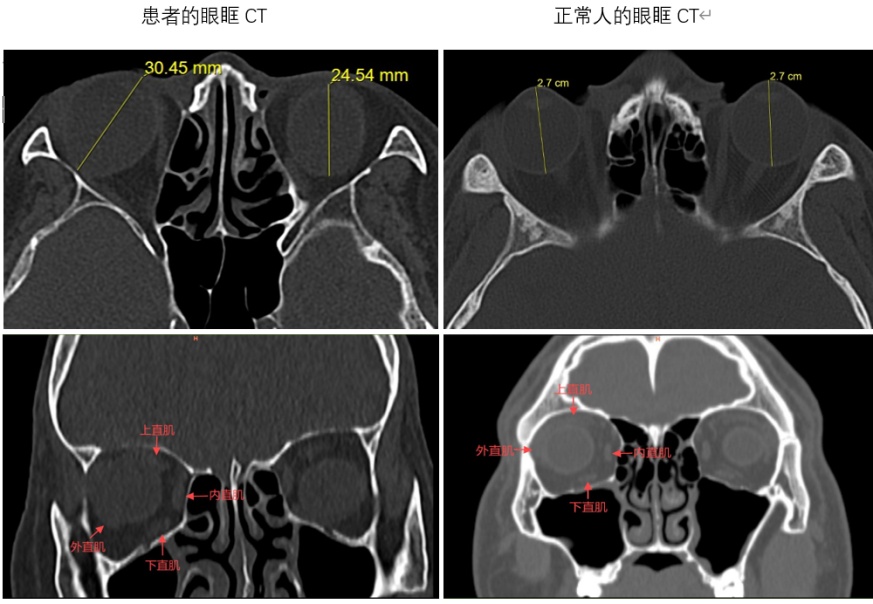

重眼综合征是一种复杂的固定性内斜视,多与高度近视、眼轴过长、眼外肌筋膜组织发育异常或退化相关。高度近视患者因眼轴过长,伴随眼外肌和筋膜组织结构变异或退行性变,导致患眼从眼周上直肌和外直肌之间较为薄弱的颞上方疝出,使眼球向内下方移动并逐渐固定,严重影响外转和上转功能。眼眶CT显示,田婆婆右眼眼轴超长,外直肌向鼻下方移位,上直肌向鼻侧移位,眼球后部自肌锥内向颞上方脱出,完全处于内下转位(图 1)。此前,临床多采用日本学者 Yokoyama 的改良肌肉联结术治疗该病症。